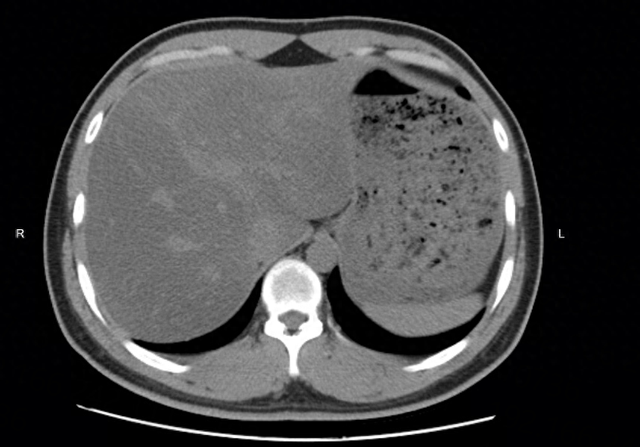

這次,她來寧波大學附屬第一醫院複查,劉女士信心滿滿,這半年來,體重減掉了5公斤,腰腹也明顯平坦了,她相信檢查報告大概不會再有脂肪肝的紅字,令她始料未及的是,B超檢查提示,脂肪肝為中重度。吃素半年,脂肪肝的程度反而加重了!